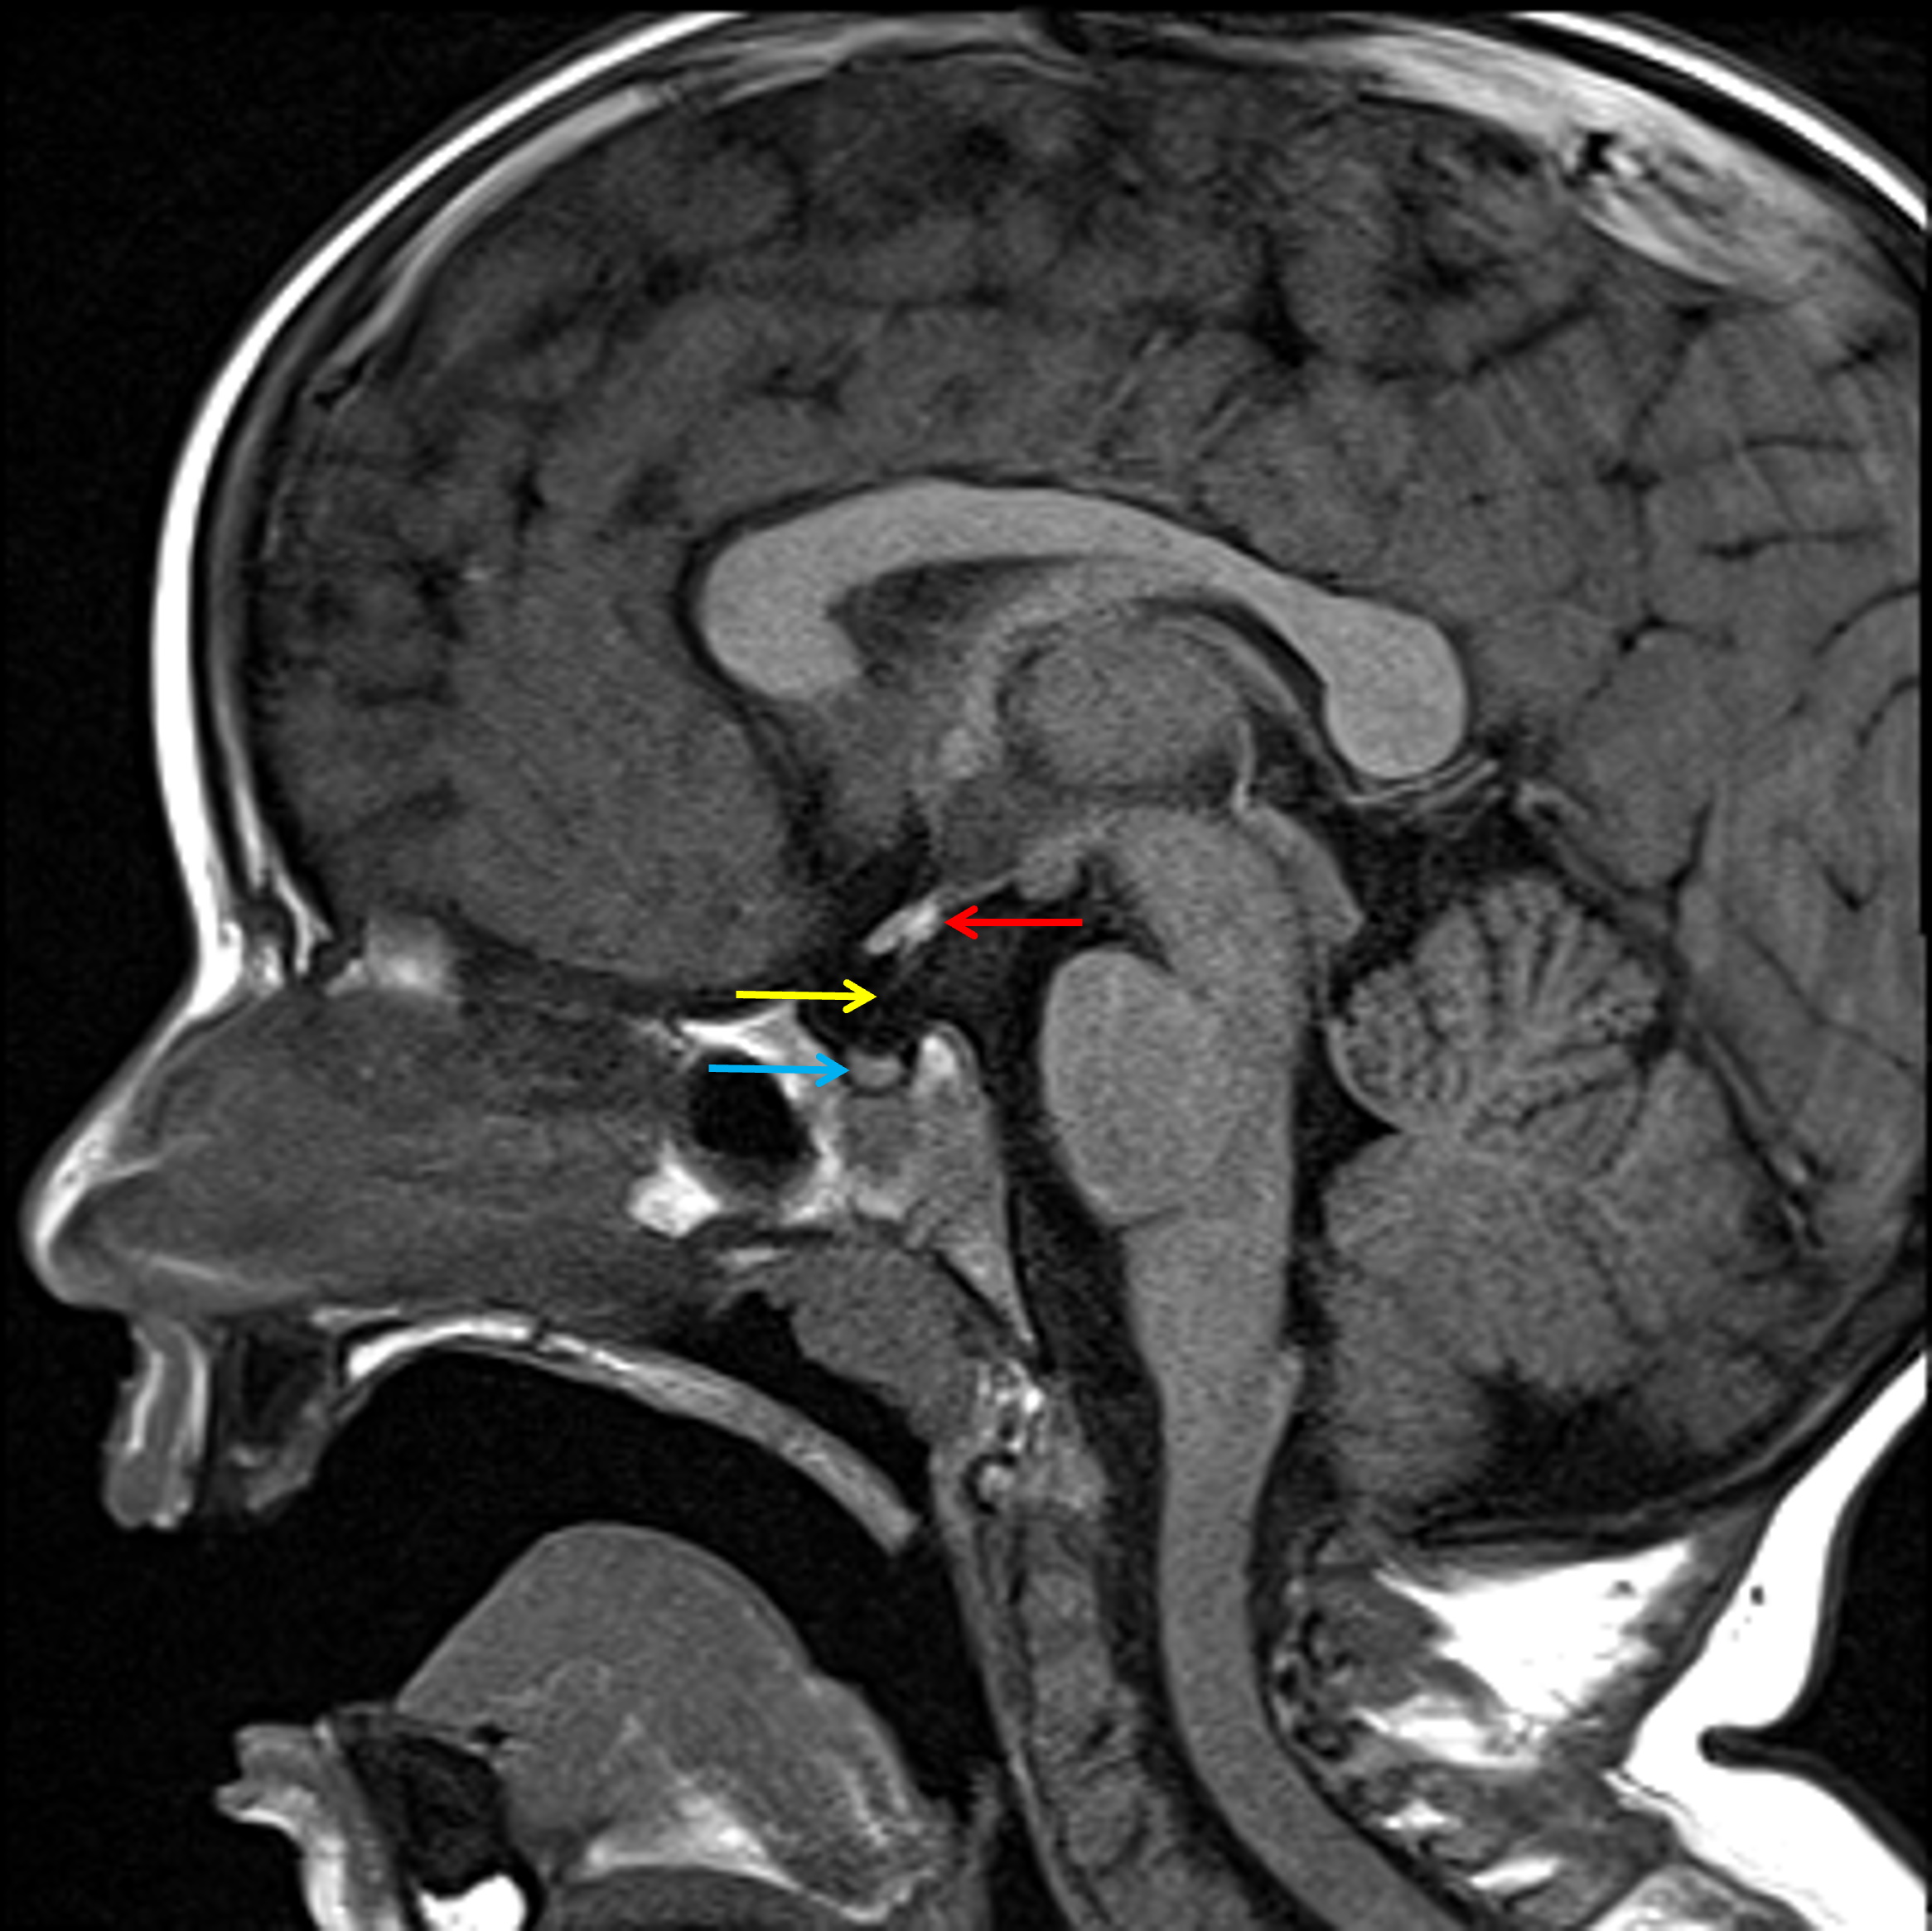

• Ectopic posterior pituitary gland, which lies at the base of the pituitary stalk

• Hypoplastic appearance of the pituitary stalk and possibly also of the adenohypophysis

• No pituitary mass

Ectopic posterior pituitary at the base of the pituitary stalk (red arrow) with hypoplastic appearance of the pituitary stalk (yellow arrow) and possibly also of the adenohypophysis (blue arrow).

Ectopic posterior pituitary